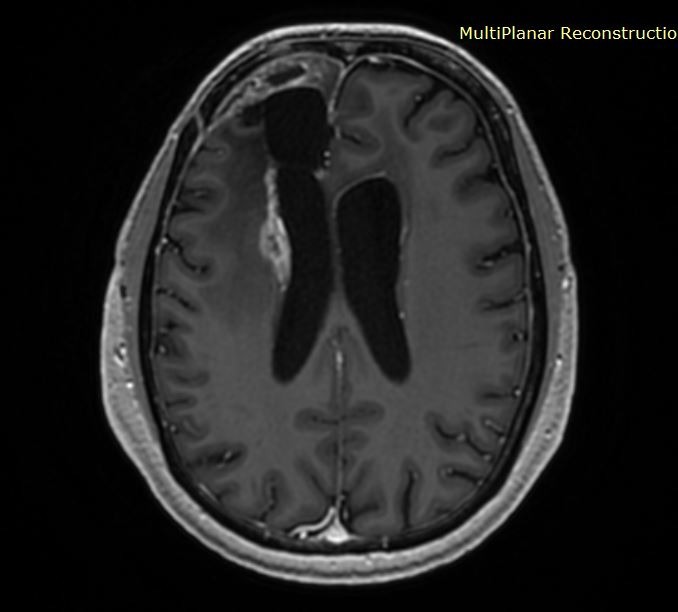

Ευμεγέθες Ενδοκοιλιακό Μηνιγγίωμα Δεξιά

Ασθενής γυναίκα, 70 ετών παρουσίασε επιληπτικές κρίσεις και αριστερή ημιανοψία. Η μαγνητική τομογραφία ανέδειξε ευμεγέθη χωροκατακτητική εξεργασία εντός της δεξιάς πλάγιας κοιλίας του εγκεφάλου. Διενεργήθη

Ενδοκοιλιακό Μηνιγγίωμα Δεξιά

Ασθενής γυναίκα, 59 ετών παρουσίασε επεισόδιο επιληπτικής κρίσης. Η μαγνητική τομογραφία ανέδειξε ευμεγέθη χωροκατακτητική εξεργασία εντός της δεξιάς πλάγιας κοιλίας του εγκεφάλου. Διενεργήθη διαφλοιική προσπέλαση

Ενδοκοιλιακό Μηνιγγίωμα

Ασθενής άνδρας, 49 ετών με επίμονες κεφαλαλγίες και τον τελευταίο καιρό και διαταραχές όρασης αριστερά. Η μαγνητική τομογραφία ανέδειξε χωροκατακτητική εξεργασία εντός της αριστερής πλάγιας